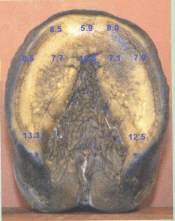

Die linken Vorderhufe von drei Wildpferdepopulationen aus Lebensräumen mit weichen (n=10), hartem (n=10) und gemischt hart-weichem Untergrund (n=10) wurden in vitro mit Hilfe einer hydraulischen Presse belastet. Die Duckverteilung wurde mit einer RDfootscan Druckrnessplatte gemessen. Die Sohlendicke wurde an 12 Punkten auf der Sohlenfläche gemessen, und zwar an Wildpferden aus Lebensräumen mit weichem Untergrund (n=10) und hartem Untergrund (n=l0) sowie an Vollblutpferden aus Haltung in menschlicher Obhut (n=20).

Zusätz1ich untersuchten wir die genaue Morphologie der dermalen und epidermalen Sohle der Hufe von Wildpferden und domestizierten Vollblutpferden. Diese Studie ergab einen signifikanten Unterschied in der Sohlendicke(Bilder1) zwischen den drei Populationsgruppen aus verschiedengründigen Lebensräumen. Wildpferde aus hartgründigen Lebensraumen hatten durchschnittlich eine dickere Sohl als Wildlebende aus weichgründigen Lebensräumen Außerdem hatten beide Wildpferdepopulationen eine höhere durchschnittliche Sohlendicke als die Vollblutpferde aus menschlicher Obhut. Die Sohle war am Rand nahe der Hufwand dicker als in der Mitte. Dies stimmt mit den Ergebnissen der Belastungsstudie überein, die darauf hinwies, dass eine erhöhte Sohlendicke mit den Bereich stärkster Lastaufnahme und damit auch höchster Abnutzung korrelierte. Die Daten implizieren, dass es als Reaktion auf biomechanische Rückmeldungs-Mechanismen verschiedene Wachstumsraten des Sohlenhorns innerhalb der Sohlenfläche geben könnte.

| (Epidermale Sohlendicke eines Brumbys aus Lebensraum mit hartem Untergrund | (Epidermale Sohlendicke eines Brumbys aus Lebensraum mit weichem Untergrund | (Epidermale Sohlendicke eines Vollblutpferdes |

Diese Studie beschreibt die Morphologie der Sohle des Pferdehufs detaillierter, als das bis dahin der Fall war. Die Sohlendicke variierte zwischen den Pferdepopulationen, aber die Form und Verteilung des Sohlenmaterials waren bei allen Pferden ähnlich. Die epidermale Sole ist eine gewölbeförmige Struktur, welche der Kontur des darüber liegenden Hufbeins folgt. Die durchschnittliche Dicke des Sohlengewölbes variierte zwischen 3 und 5,5 mm, je nach Population. Die Region mit der dicksten Sohlenepidermis lag am Sohlenrand neben der Verbindung zur weißen Linie. Die Sohlenepidermis wurde vom Rand zur Mitte enger. Die durchschnittliche Epidermisdicke stieg bei jeder Population vom dorsalen zum palmaren Huf an, wiederum der Kontur der palmaren Hufbeinoberfläche folgend. Die Sohlendermis folgte in der Dicke einem ähnlichen Muster wie die Epidermis. Der Durchschnittswert für die Dicke der Sohlendermis war am Sohlenrand am höchsten (3,4 mm) und in Richtung Mitte am dünnsten (2,7 mm).